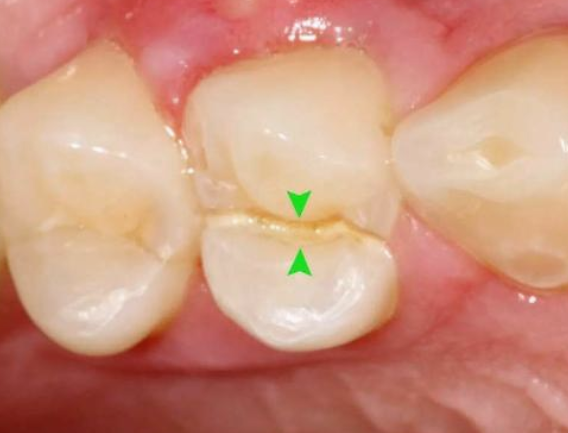

02、根管調(diào)節(jié)的適應(yīng)癥牙髓炎:牙髓因細(xì)菌感染而發(fā)炎。在密封的牙髓腔中,牙髓通常不會(huì)被細(xì)菌感染。當(dāng)牙齒因齲齒而開(kāi)孔時(shí),該孔太深,外部細(xì)菌會(huì)侵入牙髓腔,從而感染骨髓。根尖周炎:牙髓感染細(xì)菌后,細(xì)菌將通過(guò)根尖孔侵入牙槽骨,導(dǎo)致根尖周?chē)M織發(fā)炎。只要去除感染的牙髓,根尖的炎癥就會(huì)消退。牙髓裸露:當(dāng)牙齒折斷并且牙齒的神經(jīng)暴露時(shí),通常需要進(jìn)行根管調(diào)節(jié)。03、根管調(diào)節(jié)的步驟1、術(shù)前拍攝X線(xiàn)片:在根管調(diào)節(jié)過(guò)程中,在根管調(diào)節(jié)術(shù)前拍X線(xiàn)片,可以幫助診斷,了解髓室的位置和根管數(shù)目及形態(tài),測(cè)量根管工作長(zhǎng)度。